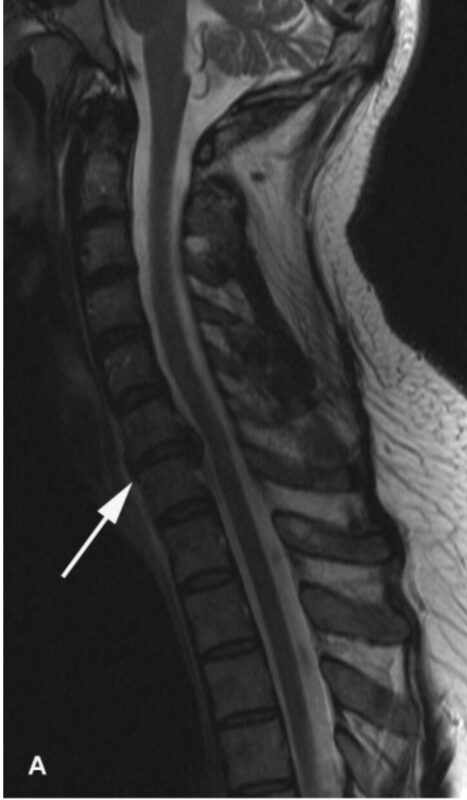

Nhìn chung, các kết quả lâm sàng gợi ý nhiều đến bệnh lý rễ thần kinh C7 bên phải và có thể ảnh hưởng nhẹ ở C6. Các nghiên cứu điện sinh lý đã xác định dẫn truyền vận động và cảm giác thần kinh trụ và thần kinh giữa bình thường ở bên phải và bên trái. Độ trễ sóng F dây thần kinh giữa và trụ bên phải và bên trái nằm trong phạm vi bình thường. Điện cơ kim của cơ tam đầu, nhị đầu, và cơ duỗi các ngón chung bên phải đều bình thường. Đánh giá cơ cạnh cột sống đã bị trì hoãn vì bệnh nhân bị đau. Chụp cộng hưởng từ cột sống cổ [Hình 1] xác định thoát vị đĩa đệm bên phải ở mức C6–7 gây ra hẹp nặng lỗ liên hợp thần kinh bên phải, không có chèn ép tủy sống đáng kể. Bệnh nhân được giới thiệu để cân nhắc phẫu thuật thần kinh lấy bỏ đĩa đệm C6-7.

Hình 1. Hình ảnh MRI cột sống cổ của bệnh nhân được mô tả trong bài này. Hình A là hình T2 đứng dọc cho thấy lồi đĩa đệm C6-C7 lấn vào khoang dưới nhện cổ. Hình ảnh B và C cho thấy đĩa lồi ra trên hình ảnh T1(B) và T2 (C). Có vết ấn nhẹ ở tủy sống nhưng không bị chèn ép đáng kể. Hình D là mặt cắt ngang của đĩa đệm thoát vị cho thấy giảm khoang dưới nhện lỗ liên hợp ở bên phải (mũi tên).